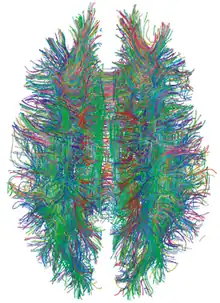

| Diffusion tensor | DTI | Mainly tractography (pictured) by an overall greater Brownian motion of water molecules in the directions of nerve fibers.[21] |

Diffusion weighted

Diffusion MRI measures the diffusion of water molecules in biological tissues.[41] Clinically, diffusion MRI is useful for the diagnoses of conditions (e.g., stroke) or neurological disorders (e.g., multiple sclerosis), and helps better understand the connectivity of white matter axons in the central nervous system.[42] In an isotropic medium (inside a glass of water for example), water molecules naturally move randomly according to turbulence and Brownian motion. In biological tissues however, where the Reynolds number is low enough for laminar flow, the diffusion may be anisotropic. For example, a molecule inside the axon of a neuron has a low probability of crossing the myelin membrane. Therefore, the molecule moves principally along the axis of the neural fiber. If it is known that molecules in a particular voxel diffuse principally in one direction, the assumption can be made that the majority of the fibers in this area are parallel to that direction.

The recent development of diffusion tensor imaging (DTI)[43] enables diffusion to be measured in multiple directions, and the fractional anisotropy in each direction to be calculated for each voxel. This enables researchers to make brain maps of fiber directions to examine the connectivity of different regions in the brain (using tractography) or to examine areas of neural degeneration and demyelination in diseases like multiple sclerosis.